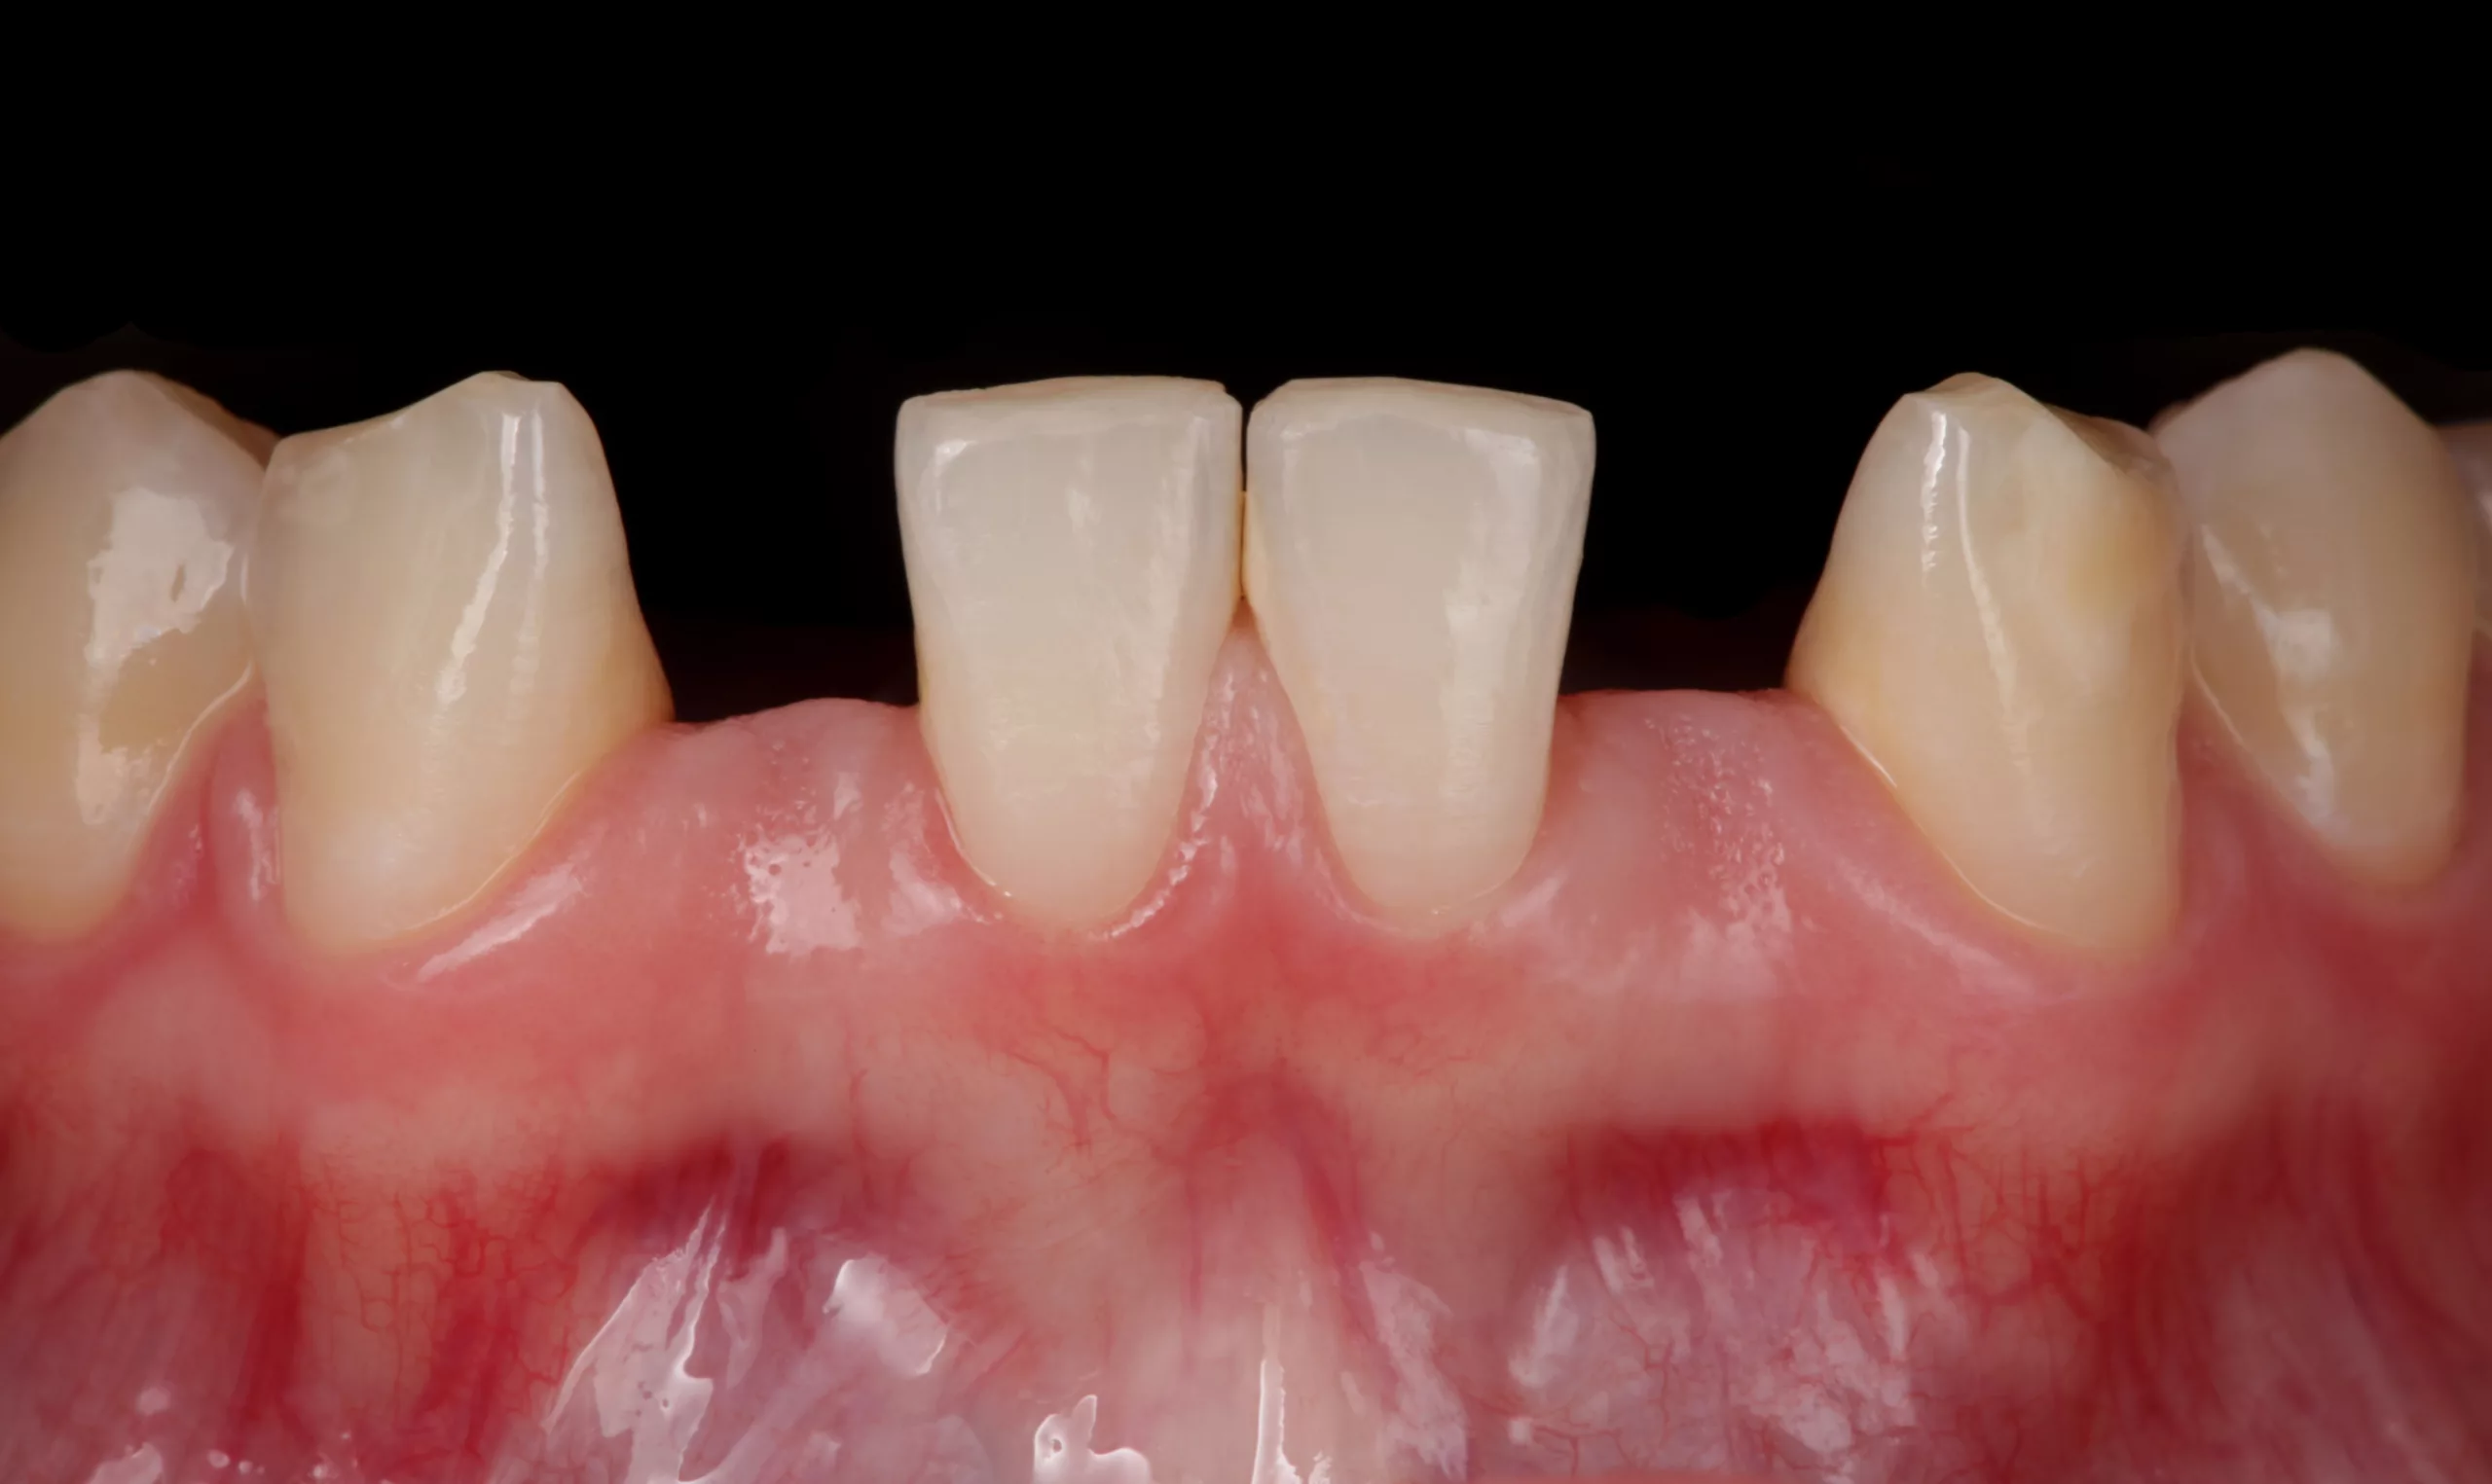

Im Anschluss an die Präparation findet die Pontic-Ausformung statt (Abb. 7). Im Idealfall steht ausreichend Gewebe in vertikaler und horizontaler Ausdehnung zur Verfügung und eine forcierte Ausformung mit einer grob diamantierten Kugel, einem Elektrotom oder dem Laser reicht aus. Bei wenig Gewebe im basalen Bereich des Brückengliedes sollte eine chirurgische Vorbehandlung im Rahmen der präprothetischen Vorbehandlung (z. B. Rolllappen, Bindegewebstransplantat) in Erwägung gezogen werden.

Okklusion und Artikulation können nun überprüft und ggf. angepasst werden. Abschließend folgt die Instruktion des Patienten zur effizienten Reinigung im Bereich der Adhäsivbrücke. Eine Situationsabformung mit anschließendem Situationsmodell und die fotografische Dokumentation des klinischen Ergebnisses helfen bei den Nachsorgesitzungen zur Kontrolle etwaiger Veränderungen der Pfeilerzahnstellung (Abb. 13- 15).